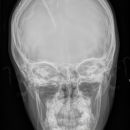

Schädel a.-p.

Fremdkörper-Lokalisation vor MRT, Shuntkontrolle

Symmetrische Abbildung beider Schädelhälften, Nasenscheidewand streng in der Mitte. Die Felsenbeine stellen sich im unteren bis mittleren Drittel der Orbita da. Felsbeinspitzen projizieren sich in die Mitte der Orbita oder eher etwas oberhalb davon.